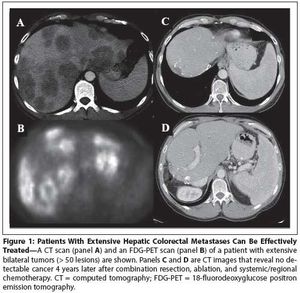

This article will review the current practice of hepatic resection for colorectal liver metastases, including the possibility of combined resection of hepatic metastases at the time of resection of the primary cancer.